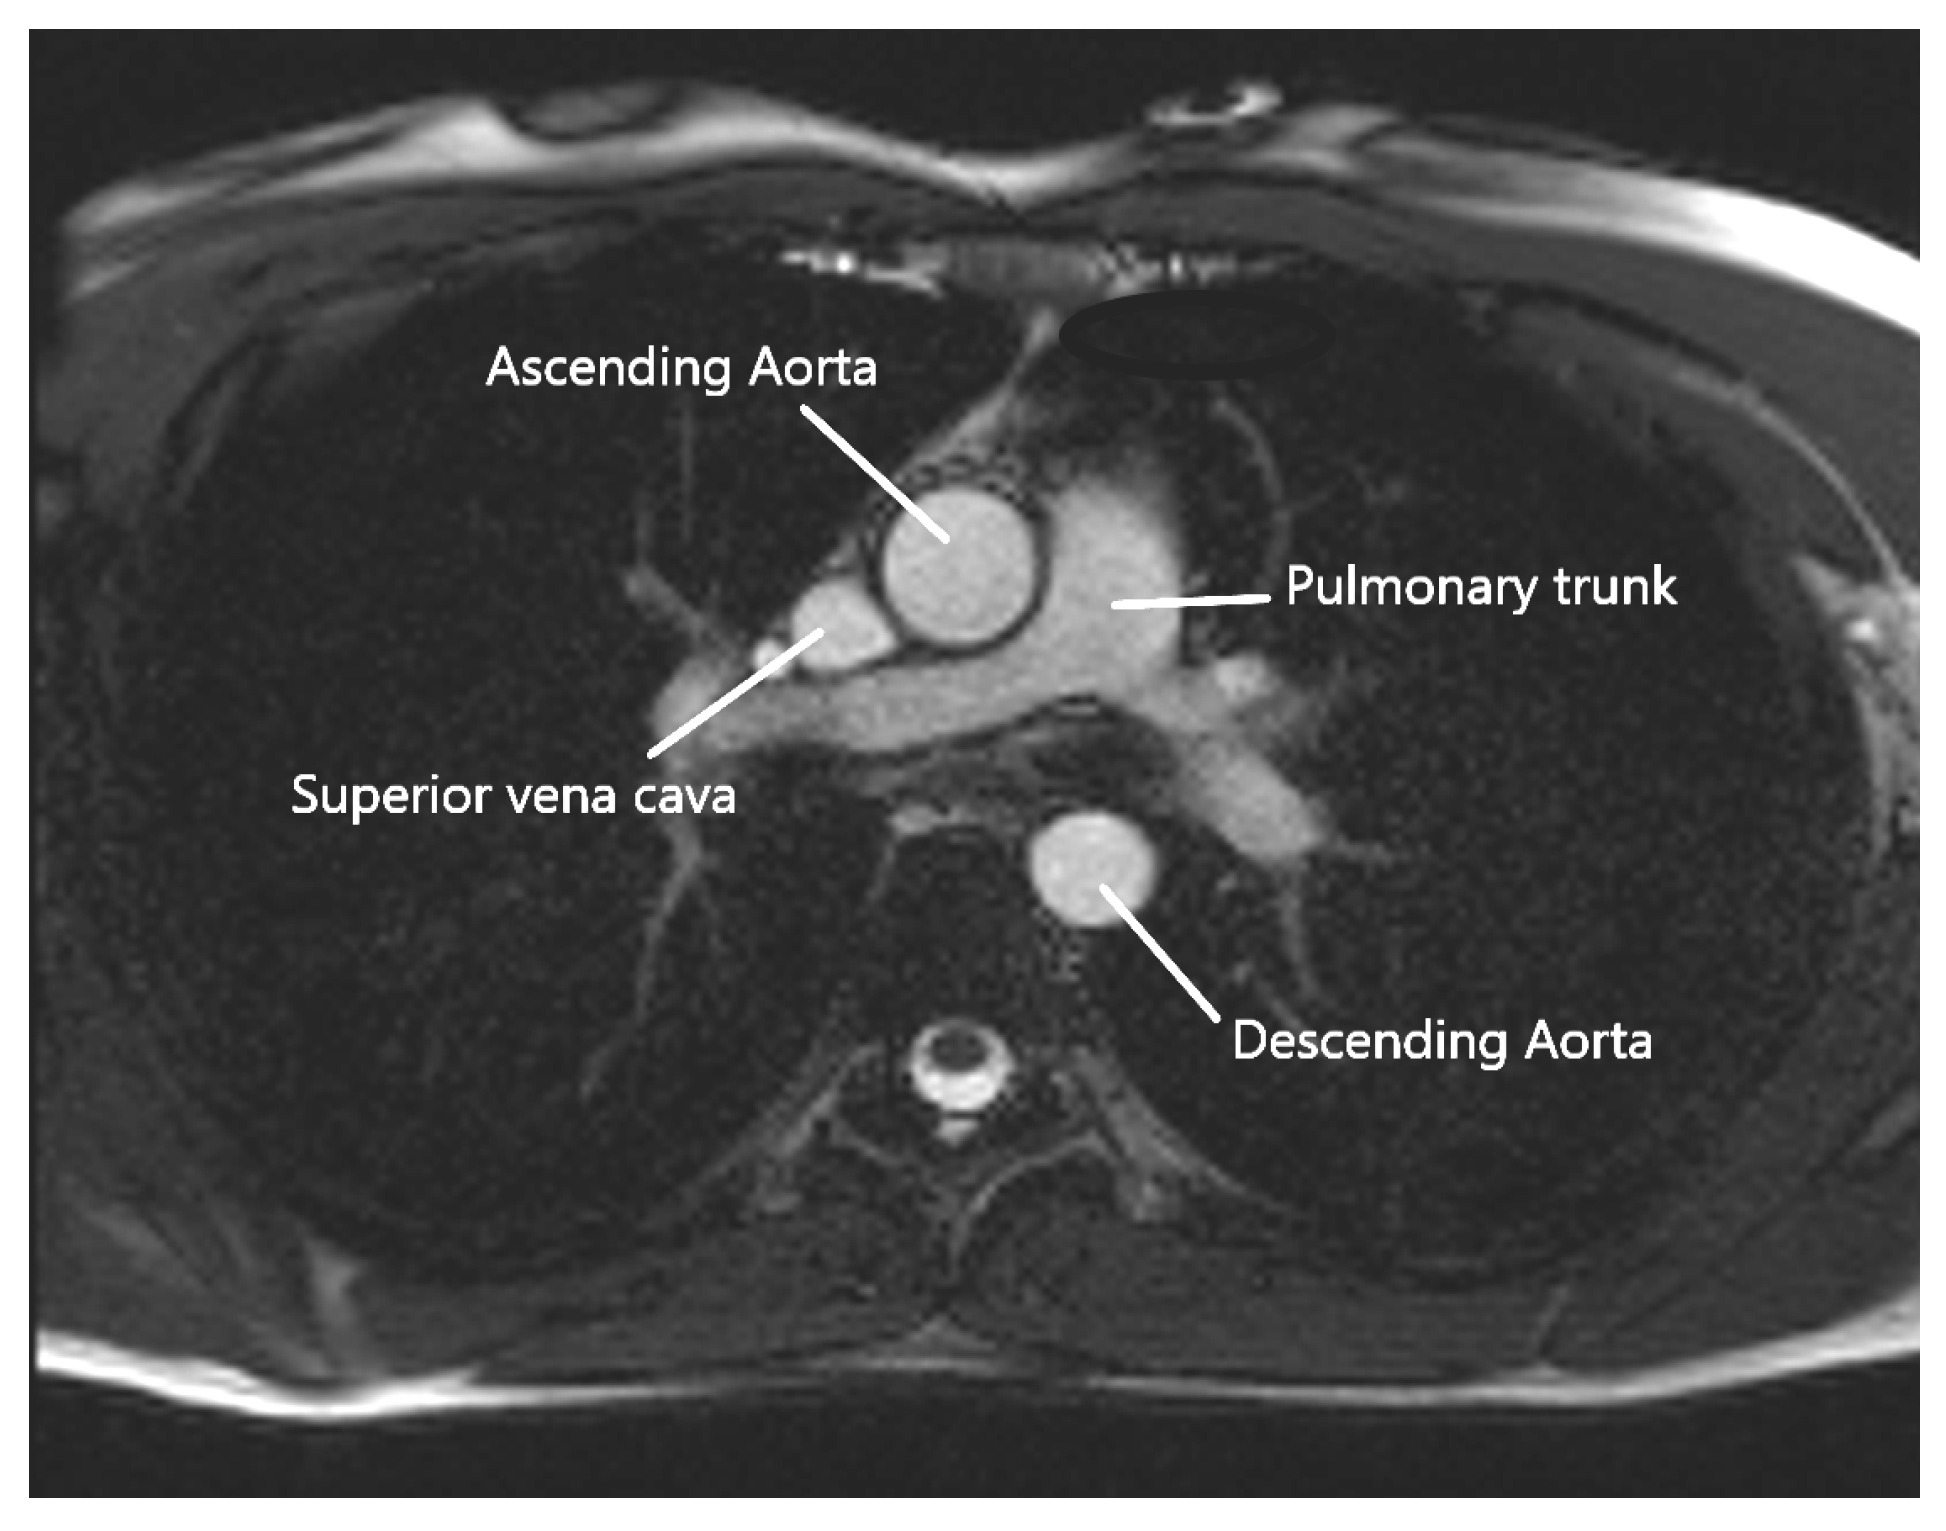

A cardiac MRI was performed before the cardiac surgery to determine, in particular, the aortic compliance. Images were collected using a 3T MRI (Skyra, Siemens Healthineers, Erlangen, Germany), with a specific acquisition in addition to the standard protocol. This acquisition is a FLASH-type sequence undertaken during a short breath-hold in the transverse plane at the level of the pulmonary artery bifurcation, as shown in Figure 1. Since it is less sensitive to noise caused by rapid or turbulent flow at 3T, this sequence was chosen over a steady state free precession (SSFP)–type sequence. This plane allows us to examine both the ascending and descending thoracic aortas. Images at all phases of the cardiac cycle were obtained with a temporal resolution of 20 ms to 34 ms thanks to a retrospective ECG-gating, with the following sequence settings: echo time of 3.42 ms, repetition time of 7.21 ms, flip angle of 12°, spatial resolution between 1.09 × 1.09 mm/pixel, and 1.25 × 1.25 mm/pixel (corresponding to a field of view ranging from 350 mm to 400 mm), and slice thickness of 5 mm. A generalized auto-calibrating partially parallel acquisitions (GRAPPA) was performed, with an acceleration factor of two. A pre-scan normalized filter and distortion correction were also applied.

Figure 1.

Axial MRI at the level of the pulmonary trunk.